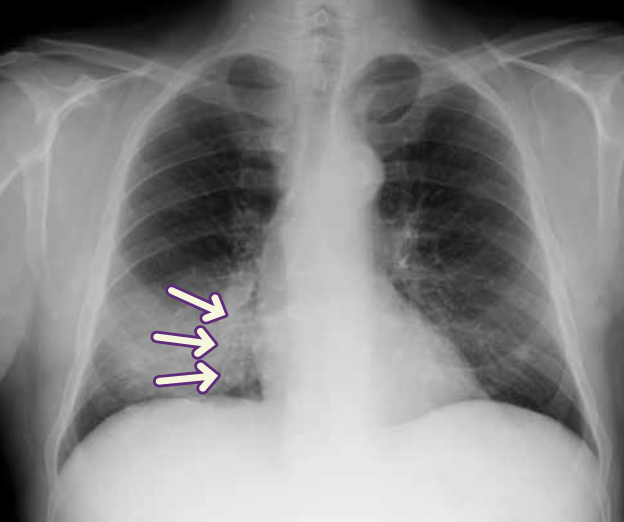

Signo de la silueta en placa de tórax PA.

Neumonía del lóbulo inferior izquierdo. La consolidación del lóbulo inferior izquierdo borra el contorno del hemidiafragma izquierdo (infiltrado retrocardiaco).